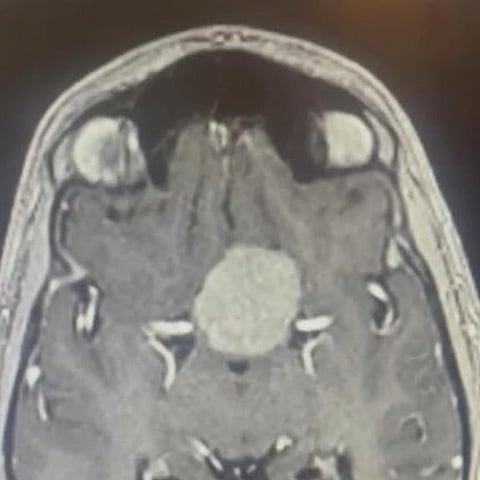

وفي التفاصيل، قام المريض بمراجعة عيادة المخ والأعصاب بسبب شكواه التي عرقلته عن ممارسة حياته الطبيعية، وبعد إجراء الفحوصات السريرية والمخبرية والإشعاعية تم اكتشاف ورم سحائي في حديبة السرج التركي في قاع الدماغ.

وعلى الفور، قرّر الفريق الطبي إجراء عملية جراحية باستخدام تقنية المجهر الدقيق تم خلالها إزالة الصفائح العظمية وفتح غشاء الأم الجافية الأم حتى الوصول إلى مكان الورم الحساس بين أهم شرايين وأعصاب الدماغ، ومن ثم تم استئصاله بالكامل دون وقوع ضرر للدماغ خلال أكثر من 4 ساعات بغرفة العمليات.